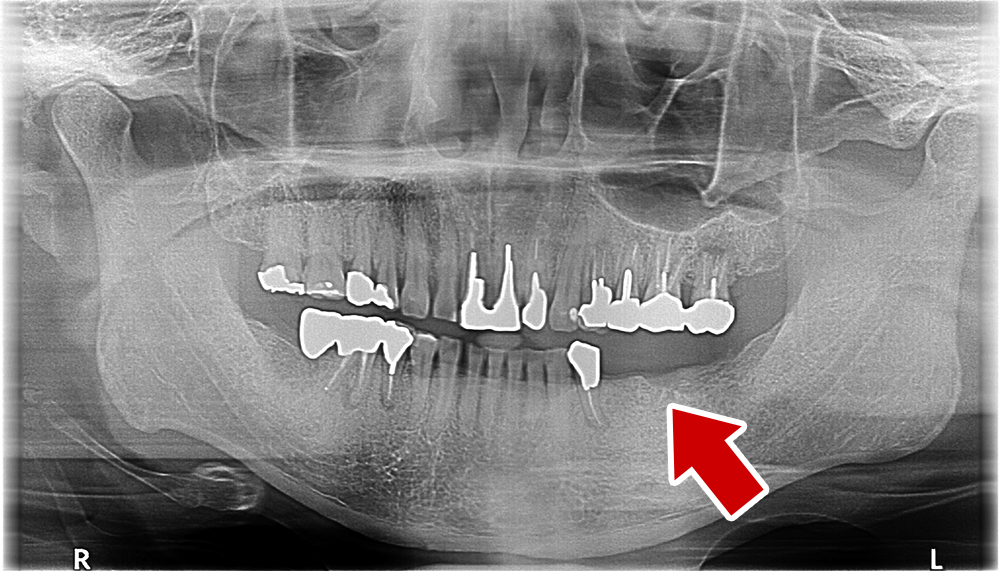

60歳 男性 歯科大学病院 教授からの紹介。ご本人は産婦人科医

- 主訴

- 左下に歯が無くて食事がしずらい

- 処置内容

- 2本インプラント埋入+再生処置。

- 治療費用

- 下顎 約80万円(税込)

- 治療期間

- 下顎:6か月

- リスク

-

術後の腫れ、痛み(ピークは3日後、1週間で軽減)

上部構造物、仮歯の破折、人工歯根脱落リスクがあります

- その他

- 歯科大学病院 教授からの紹介。ご本人は産婦人科医